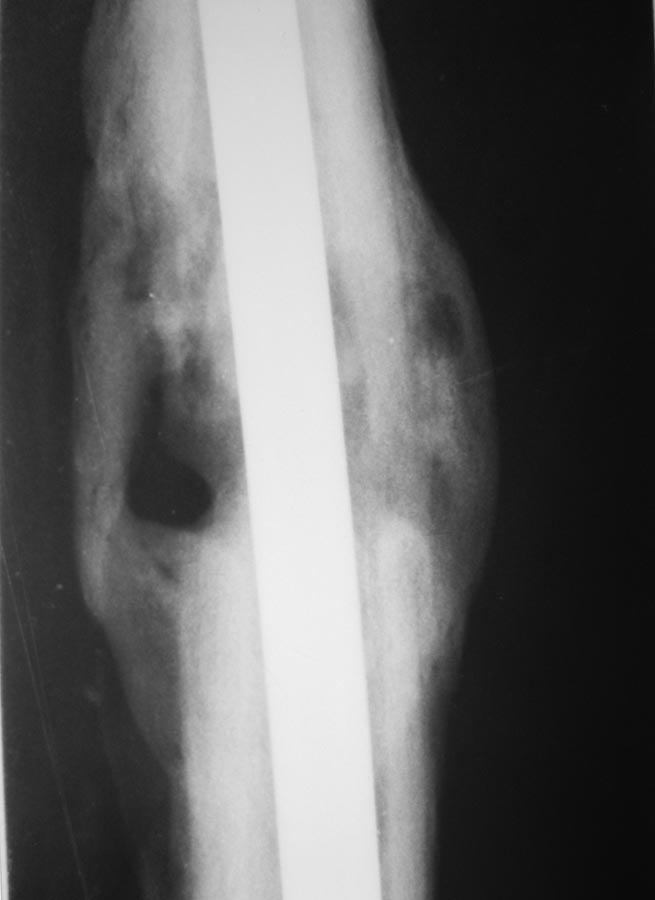

Пациент после БИОС бедренной кости.

Пациент 26 лет, около года назад получил травму в результате ДТП. По

поводу перелома диафиза бедренной кости выполнялся БИОС. Заживление ран

в области дистальных блокирующих винтов происходило вторичным

натяжением, однако, в ходе местного лечения раны зажили. Спустя 4-5 мес.

пациент обратился с болями в нижней трети бедра (проекция дистальных

блок. винтов). При RG выявлена их миграция, выполнено их удаление.

Спустя еще 4-5 мес обратился с жалобами на припухлость в

области дистального блокирования. В поликлинике сделали снимки и, с

подозрением на остеомиелит, оправили в стационар. Сегодня: местно - без

признаков инфекции. В области дистального блокирования припухлость

плотно-эластичной консистенции. При пункции получить ничего не удалось.

Лейкоциты 6,0; СОЭ - 22. СРБ-18. Температура в вечерние часы

37-37,2 Снимки представлены.